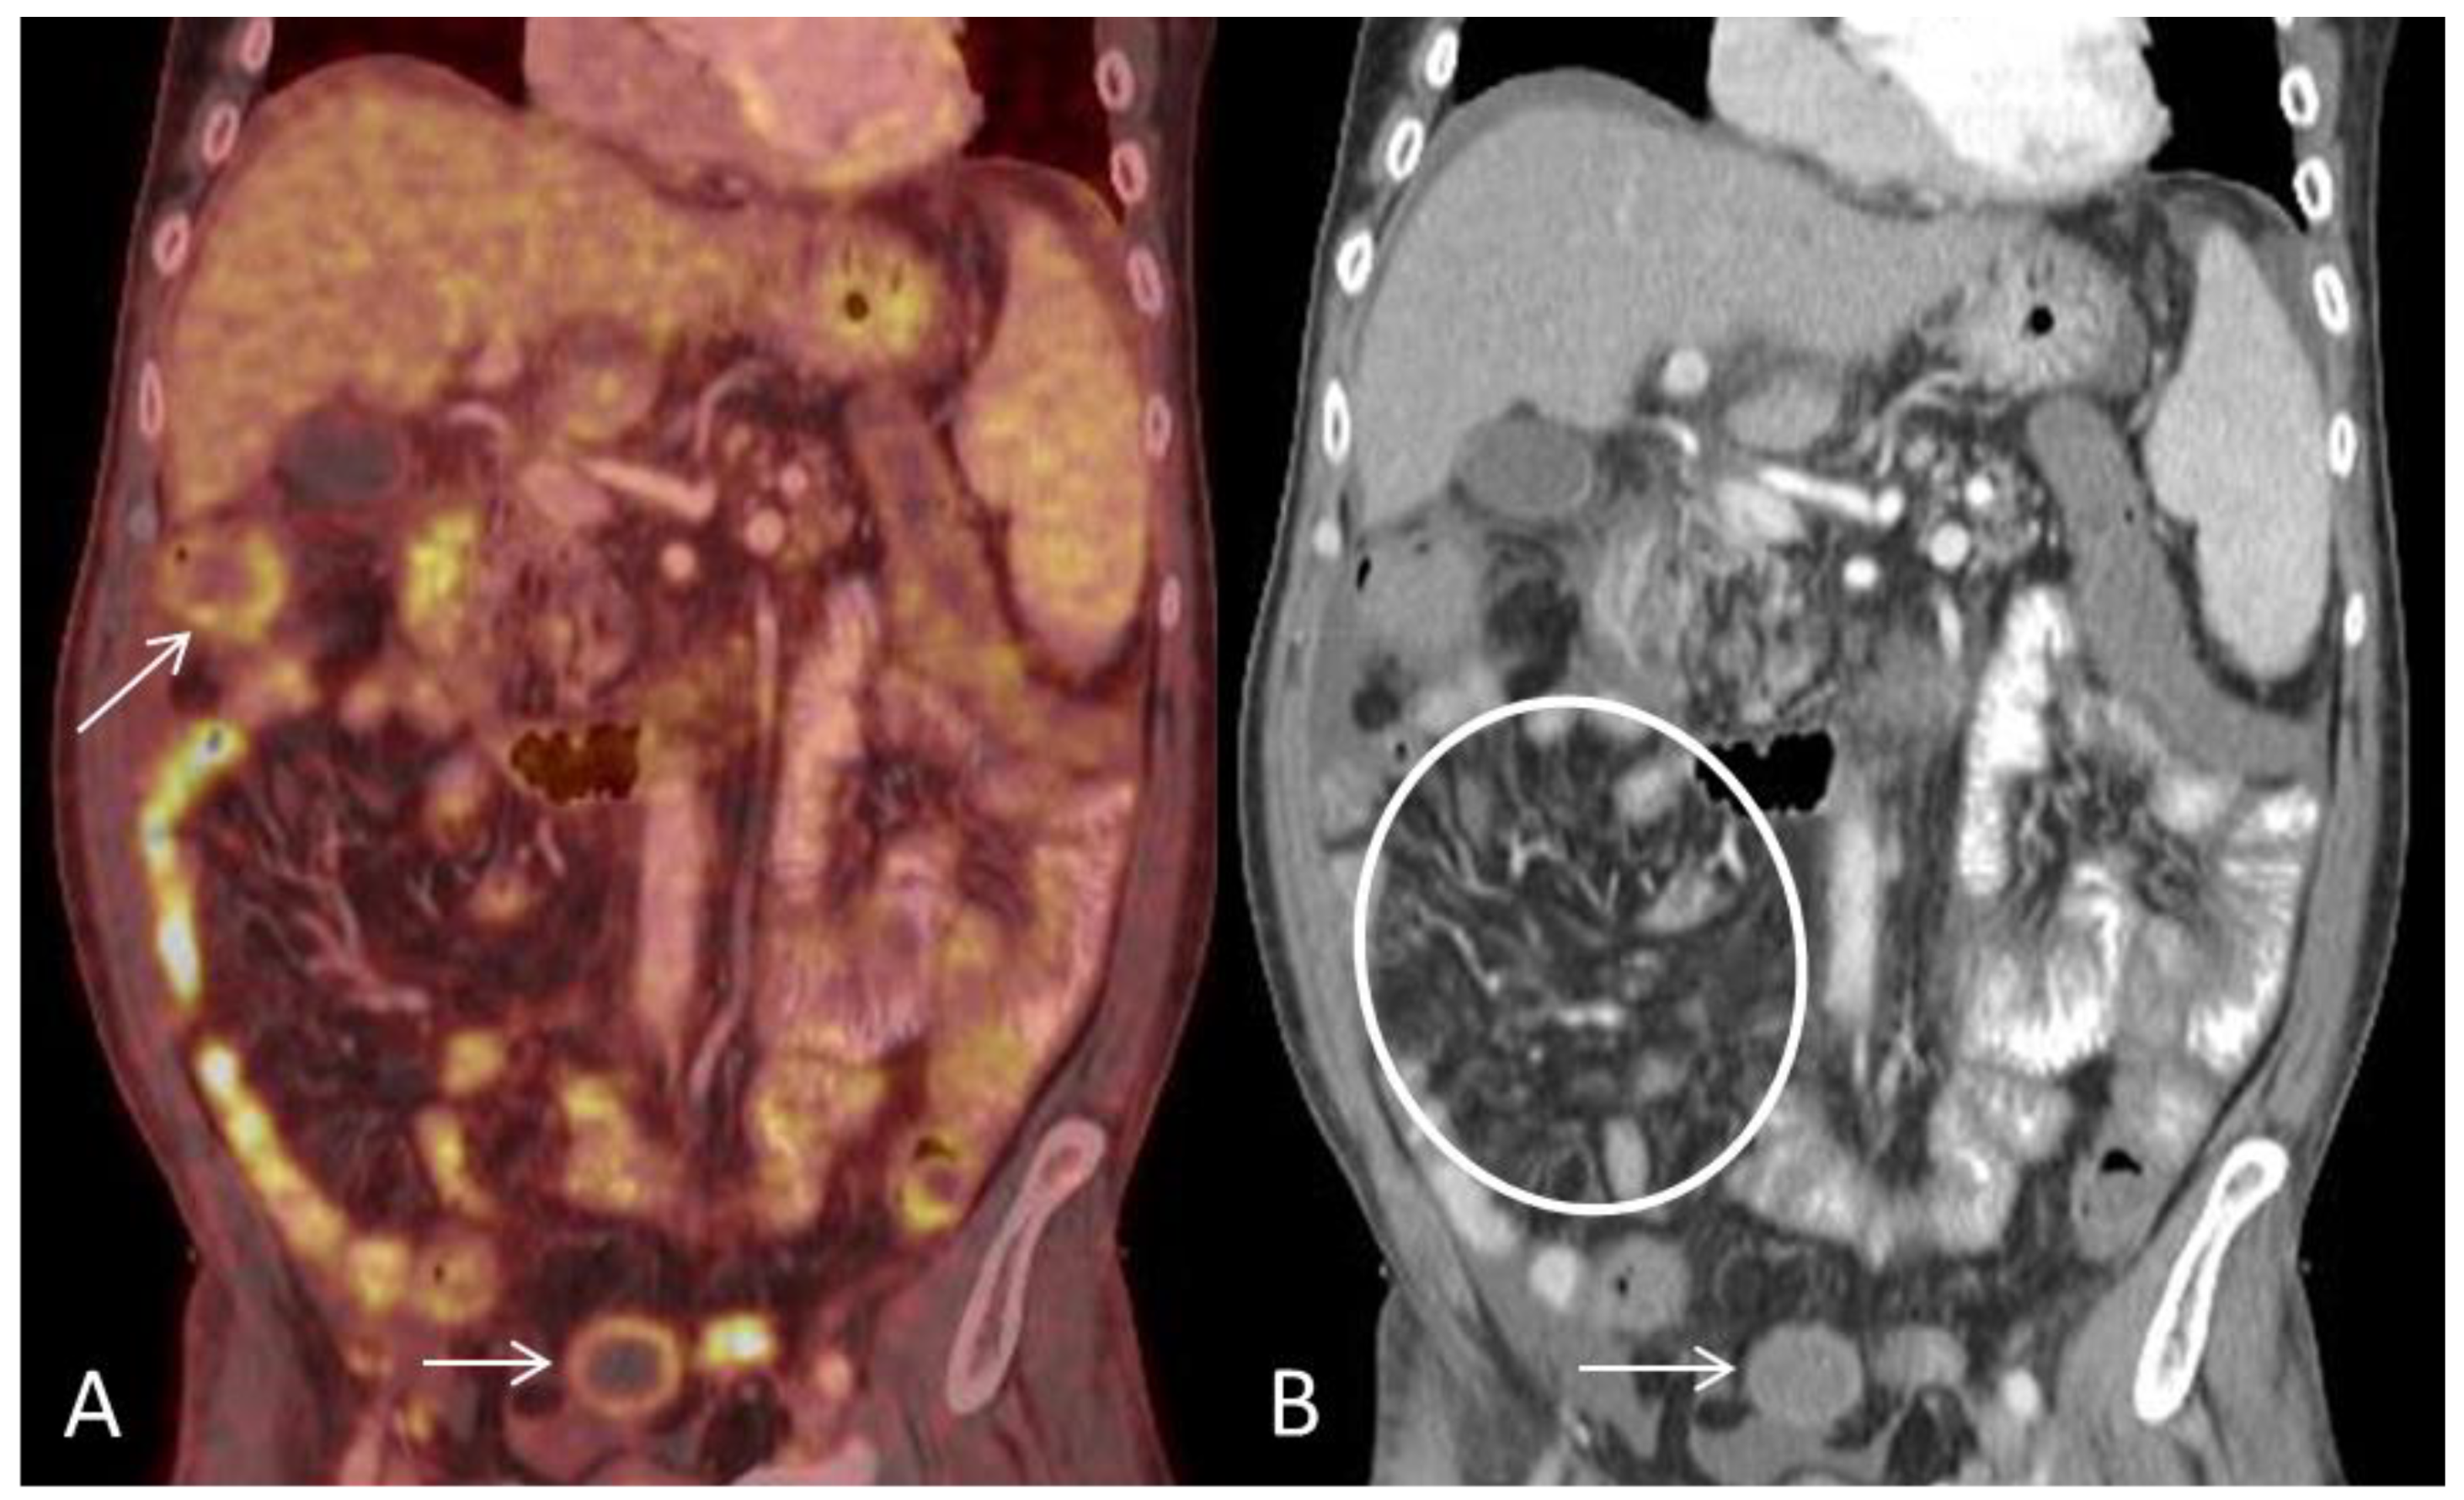

(A) Coronal PET and CT fused image demonstrates multifocal segmental pathological FDG-uptake in small-and large bowel loops. Circumferential mural pathological FDG-uptake in the large bowel (arrows). (B) Coronal CT shows engorgement of the vasa recta (circle) and mural enhancement of the large bowel (arrow). Ascites is present on the surface of the liver. Engorgement of the vasa recta is due to increased blood-flow in small arteries of inflamed bowel segments and has been reported as the most consistent extraintestinal finding in acute GIT-GVHD [2].